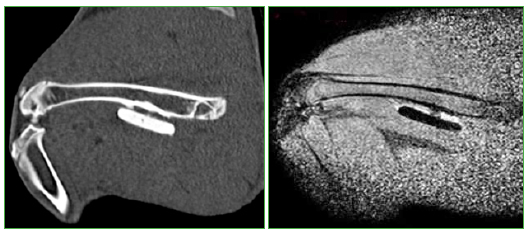

Figura 4.

Resonancia magnética. Cemento más antibióticos.

A las seis semanas, todos los conejos fueron sacrificados y se tomaron radiografías e imágenes por resonancia magnética y tomografía computarizada de ambos fémures (Figuras 3 y 4). Las radiografías y las imágenes por resonancia y tomografía fueron evaluadas por un radiólogo especialista en el sistema musculoesquelético, que midió la formación de puentes óseos e inflamación en los distintos materiales colocados en cada conejo. Las resonancias se efectuaron con un equipo Philips® Achieva 1,5 T; se utilizó una antena de rodilla de 8 canales. Las tomografías se realizaron con un tomógrafo Siemens SOMATOM Sensation multislice de 64 canales. Se determinó la formación de puentes óseos mediante cruces (x = 1/3, xx = 2/3, xxx = 3/3). Al extraer los diferentes materiales se evaluaron: el espesor de la membrana, la adherencia de la membrana al material y la formación ósea alrededor del material; estos tres aspectos fueron clasificados por los autores mediante una escala de 0 a 3 cruces, según su magnitud, donde 0 indica ausente y 3, muy marcada. Las membranas que se formaron alrededor de los implantes y el cemento fueron luego meticulosamente disecadas para no dañarlas, y se conservaron en formalina al 10%.

No hubo diferencias significativas entre los lados (derecho = cemento más corticoide, izquierdo = clavija) en las radiografías y las imágenes tomográficas (p = 0,310, p = 0,988, respectivamente). Respecto a la resonancia magnética, la mayoría de las respuestas indicaron sin osteointegración o una escala de valoración de hasta 1/3. Se destaca que el 87% de los animales a los que se les colocó clavijas no tuvieron observaciones de osteointegración debido a distorsión de la imagen o pérdida de señal producidas por la característica del material (metal), en tanto que ese mismo porcentaje mostró una respuesta de 1/3 y 2/3 de osteointegración en los animales con cemento más corticoide. Es esta tendencia la que se distinguió significativamente (p = 0,003) entre ambos (Figura 10).